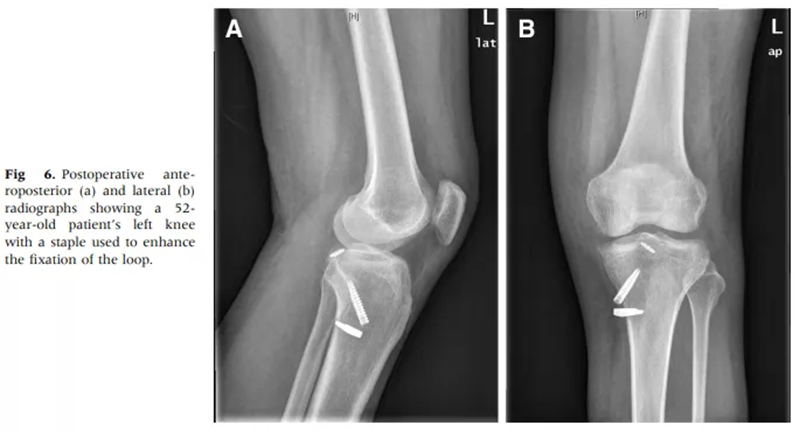

徐醫(yī)附院通過(guò)關(guān)節(jié)鏡微創(chuàng)手術(shù),只需做4個(gè)8mm左右的小切口,通過(guò)做一個(gè)直徑0.45cm、長(zhǎng)約5cm的骨隧道,將長(zhǎng)線(xiàn)環(huán)帶袢鈦板引入關(guān)節(jié)內(nèi),鈦板固定骨折,即可取得很好的穩(wěn)定性,經(jīng)過(guò)長(zhǎng)時(shí)間大規(guī)模的病例累計(jì),形成了40例的總結(jié)分析和評(píng)估,系統(tǒng)地講述了關(guān)節(jié)鏡下微創(chuàng)處理后交叉韌帶撕裂的手術(shù)方式、要點(diǎn)和治療效果,對(duì)行業(yè)發(fā)展也具有很好的借鑒意義。